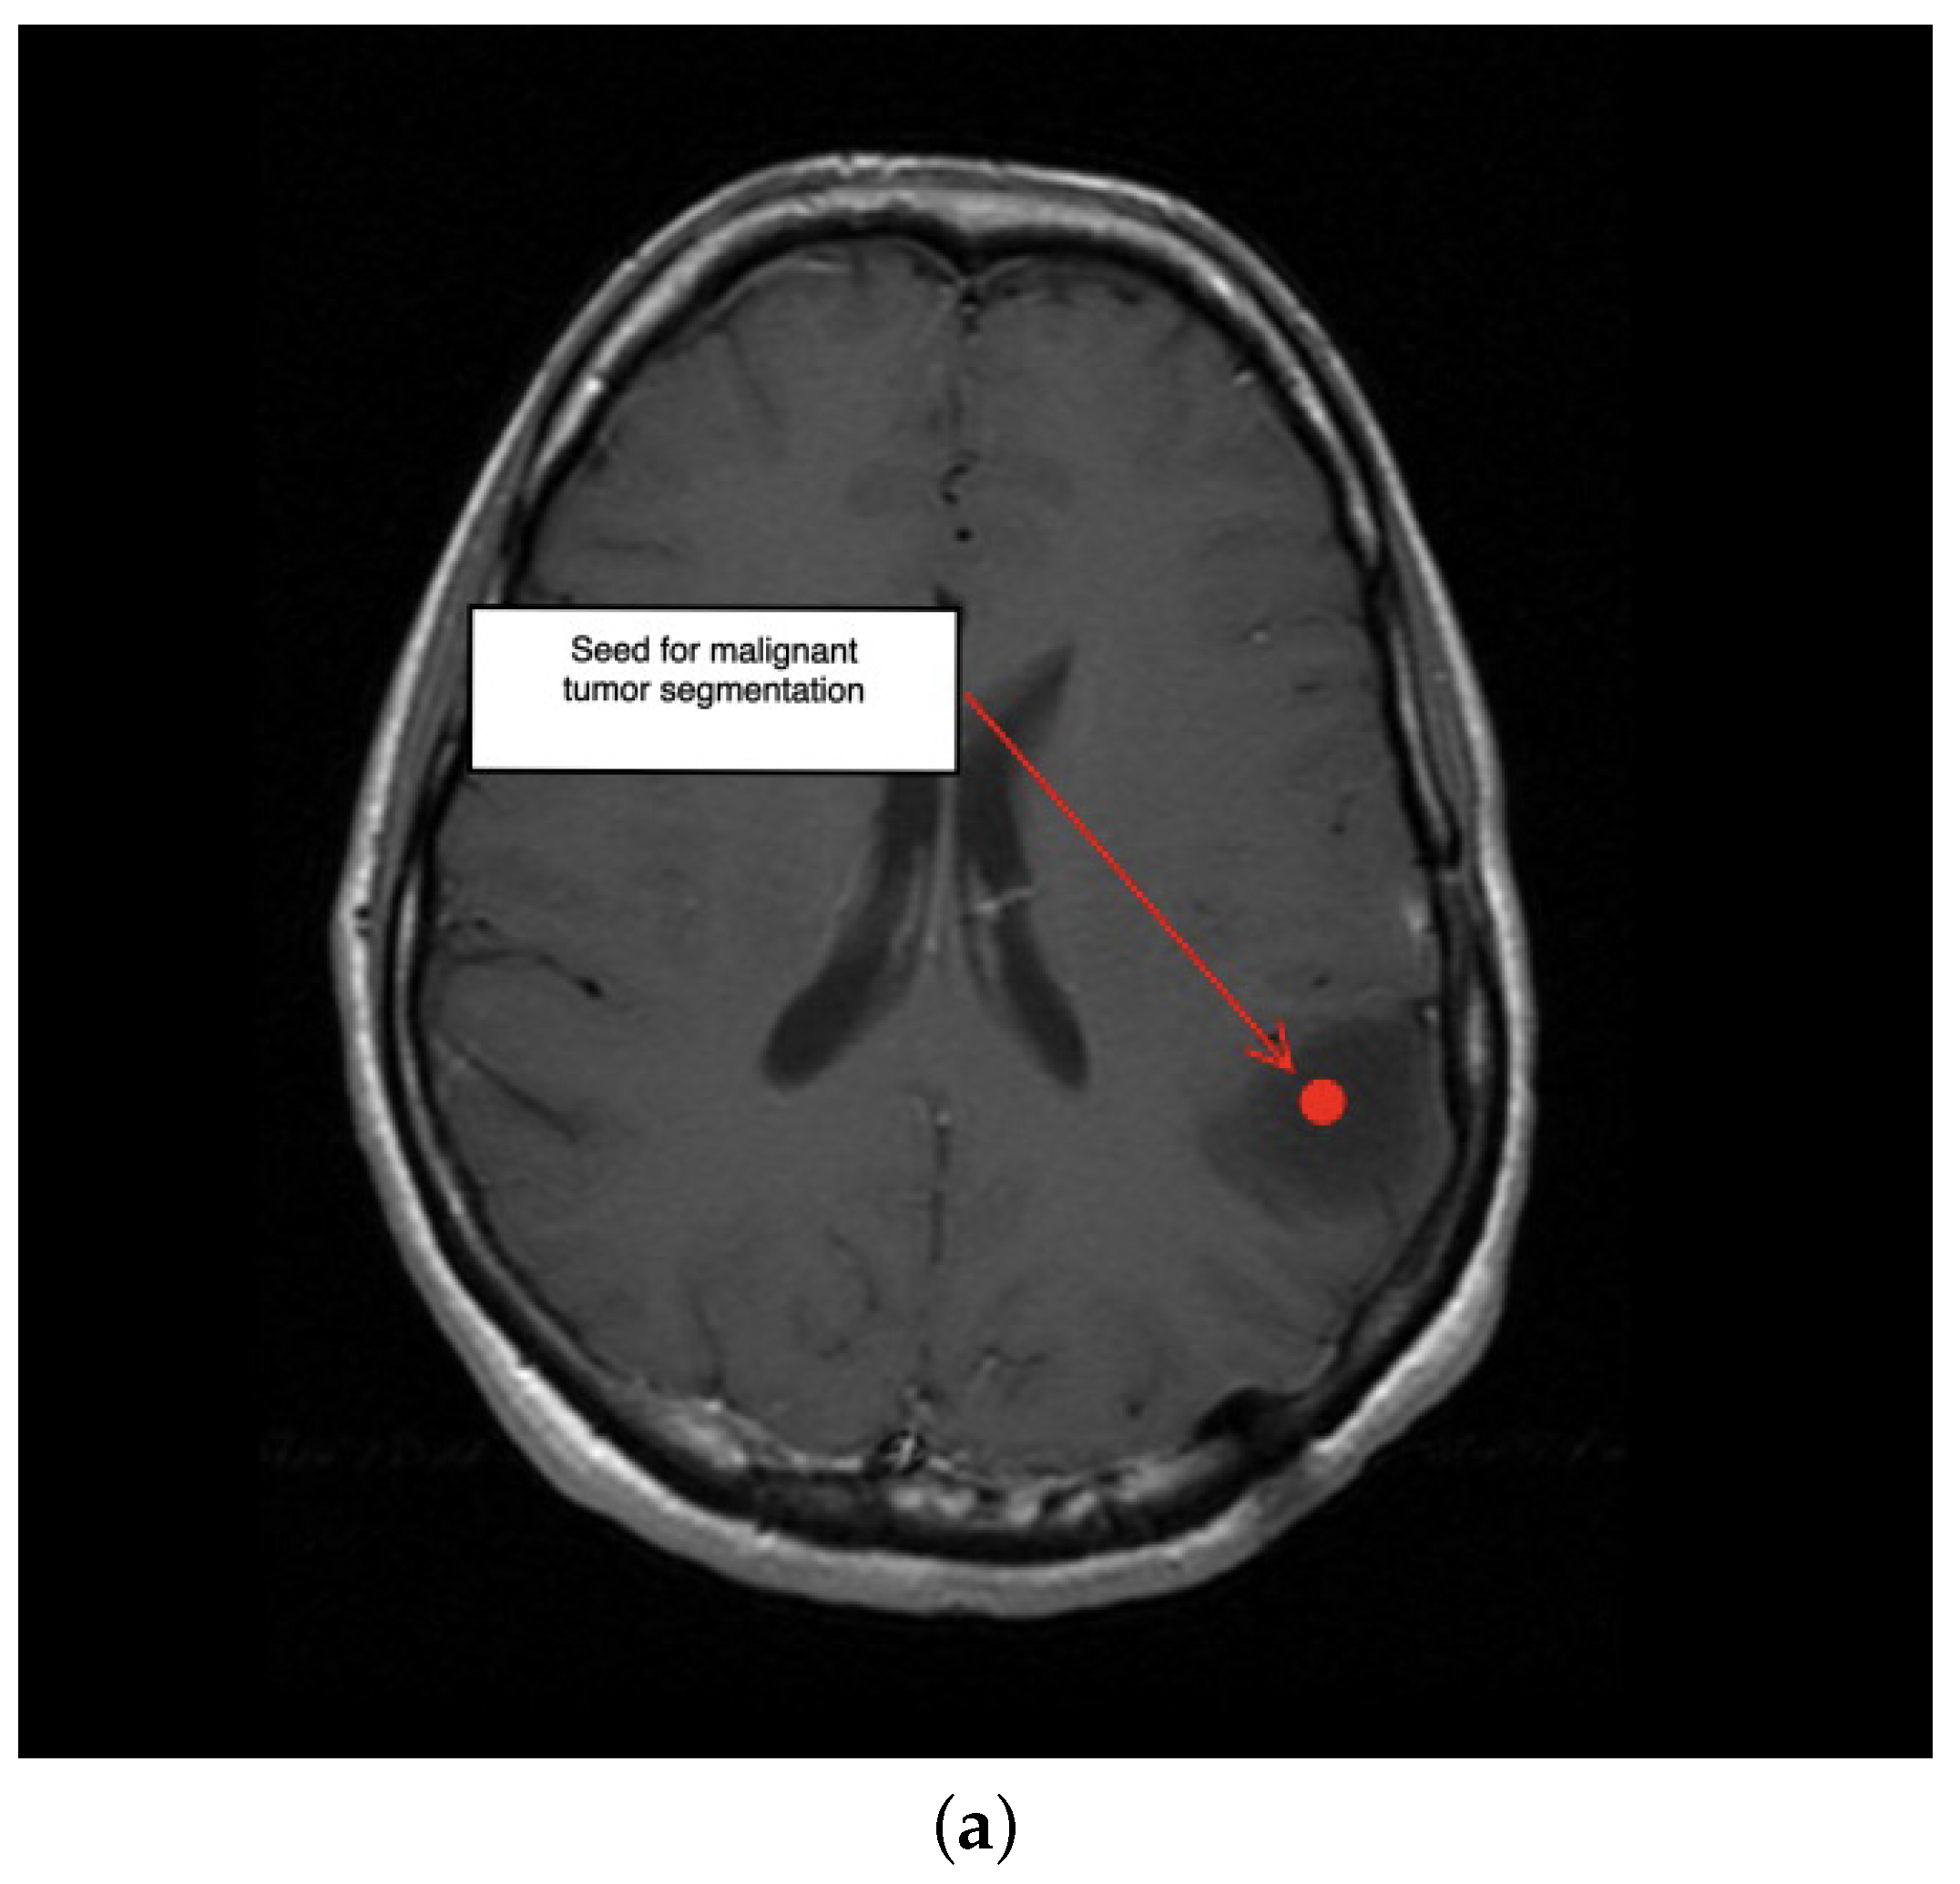

2. Description of the Methodology

3.1. First Scenario